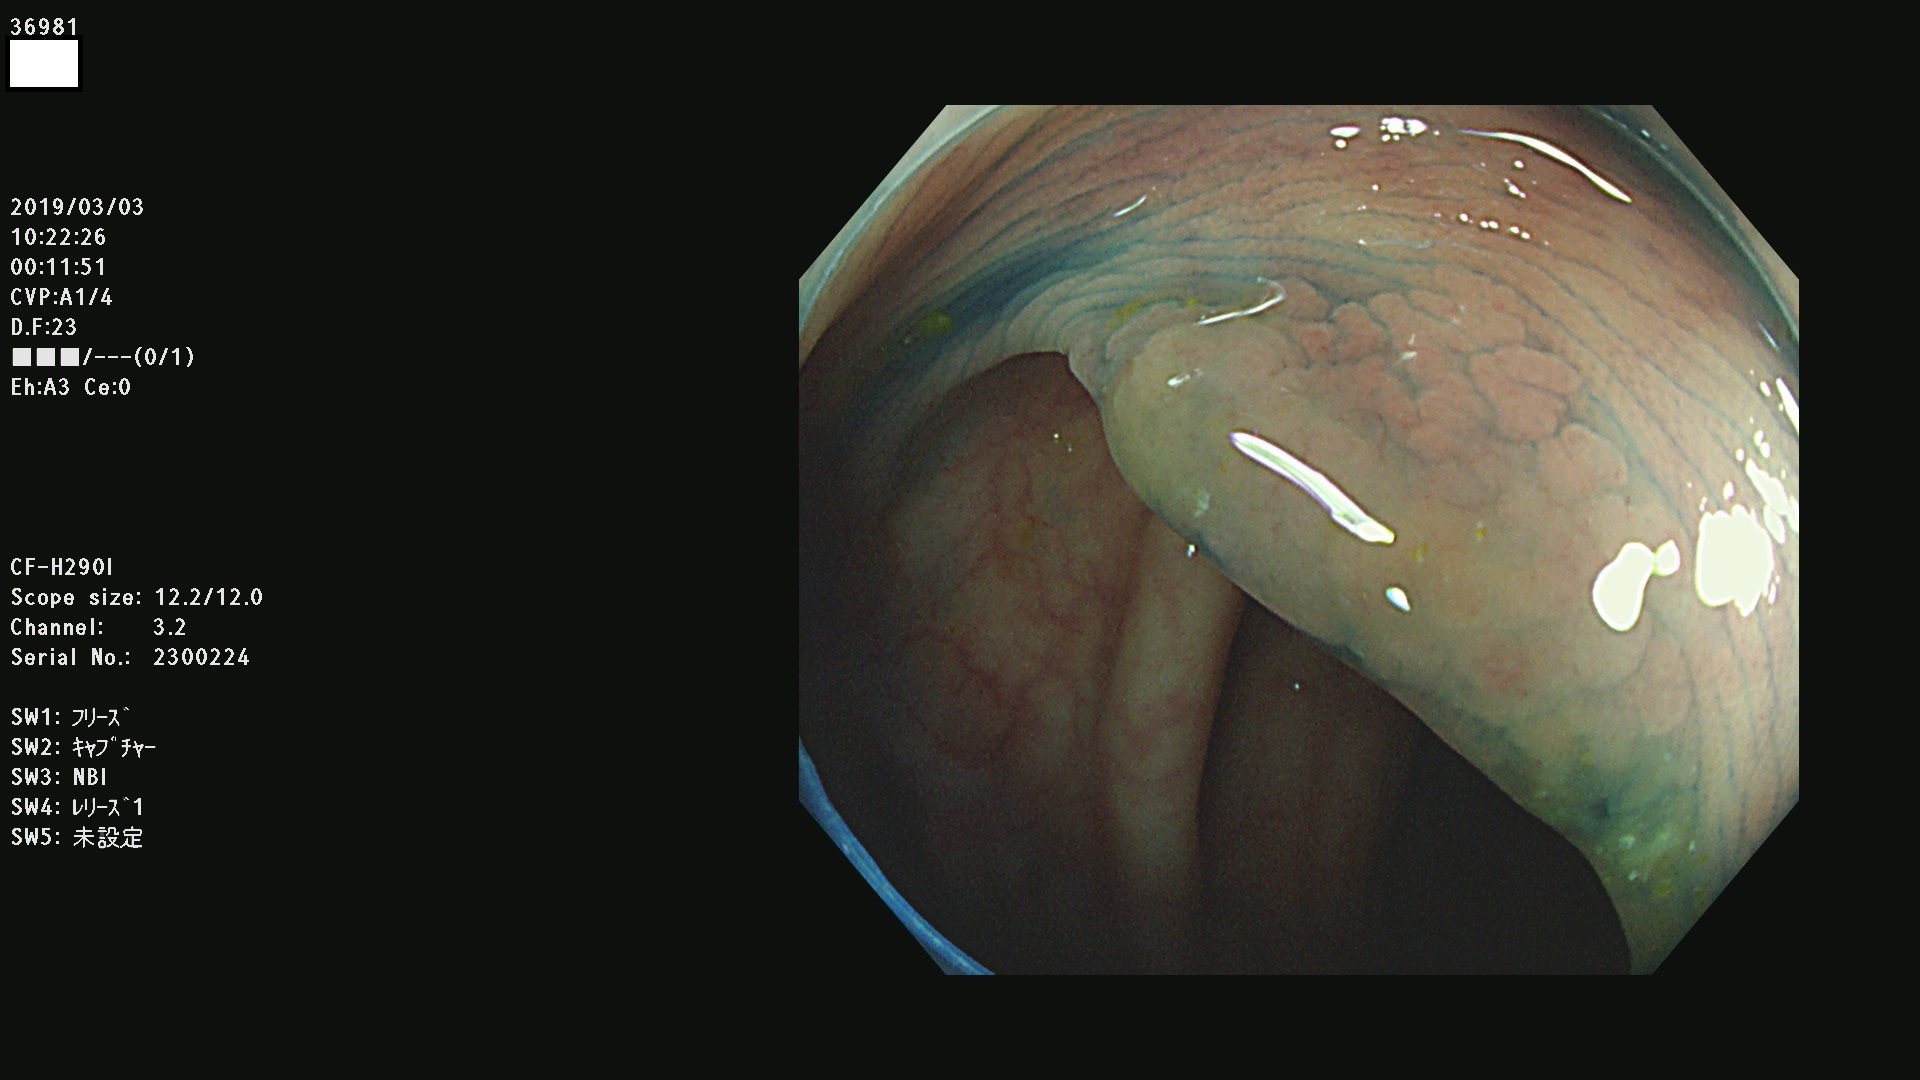

腺腫発見率 67 % (カルテ番号 36900〜36999の100名の方の検査結果で集計)大腸癌検診最新情報

以下のカルテ番号の方に腺腫(Adenoma,Group3〜5)が見つかりました(集計法)

36900 36901 36903 36904 36905 36908 36909 36910 36911 36913 36914 36915 36916 36917 36918 36919 36920 36923 36924 36925 36927 36928 36930 36931(SSAPのみ) 36933 36935 36936 36937 36941 36943 36944 36945 36946 36949 36951 36953 36954 36955 36957 36963 36965 36966 36967 36968 36969 36970 36974 36975 36976 36977 36978 36979 36980 36981 36983 36984 36986 36987 36988 36989 36990 36991 36993 36994 36996 36998 36999

発見困難で危険性の高い平坦型病変(上記100名より抽出) ![]()